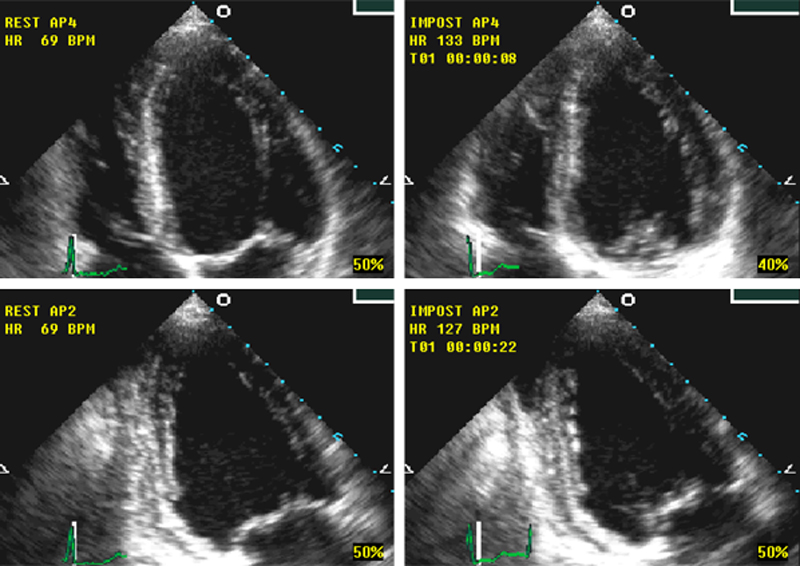

فحوصات تشخيصية لبعض امراض القلب والشرايين التاجية